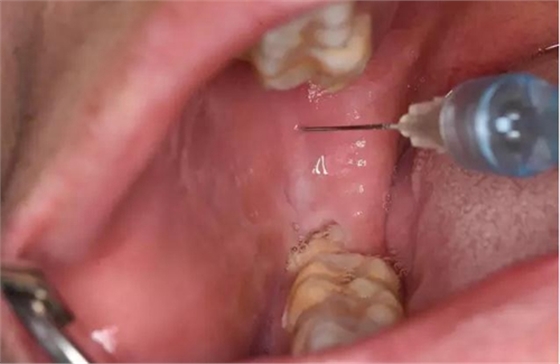

圖4.行下牙槽神經(jīng)阻滯麻醉

(2)口外局部麻醉不要將麻藥注射進膿腔內(nèi)